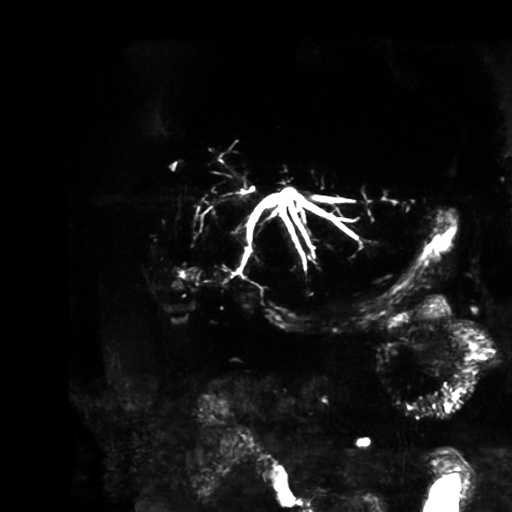

Se observa dilatación de las vías intra hepáticas a expensas de sus ramas hepáticas derecha, anterior y posterior, hepática izquierda y hepática común. El hepático común da la apariencia de estar anastomosado a un asa de intestino, lo que sugiere la posibilidad de una cirugía entero biliar.

No se logra observar el colédoco.

1. Dilatación de vías biliares intrahepáticas

2. Anastomosis entero biliar

3. Colangitis aguda